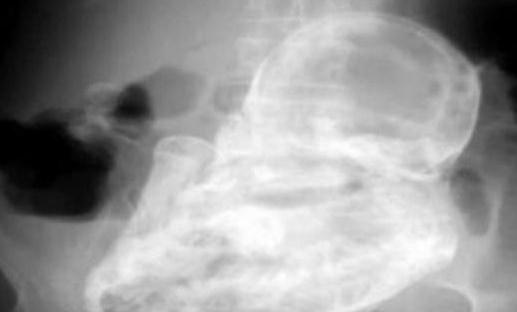

太吓人,82岁老太太查出竟怀孕40年

太吓人,82岁老太太查出竟怀孕40年 这个孕妇是位82岁的老太太,她因剧烈的腹泻而到该医院就诊。在全面的临床检查之后,医生确定她的腹部并没有结石或肿瘤。 不过,接下来的发现却让所有人吓了一...